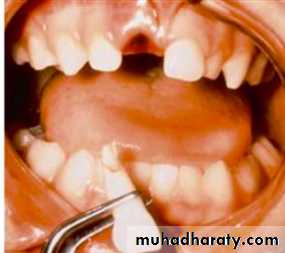

1-Tooth Avulsion

Is a Complete displacement of tooth out of socket, The periodontal ligament is severed and fracture of the alveolus may occur.

Maxillary Central Incisor- Most commonlyavulsed tooth

Associated injuries-Fracture of alveolarSocket wall

Associated injuries-Fracture of alveolar socket wall

- Injuries to the lips and gingiva

Gentle reinsertion of the tooth into the socket followStabilization

To immobilize the tooth with a semi- rigid splint for (7 -10) daysThe splint should not interfere with the patient’s capability to perform correct hygiene